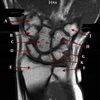

11

Q

What is letter A?

A

ANTERIOR LABRUM

How well did you know this?

1

Not at all

2

3

4